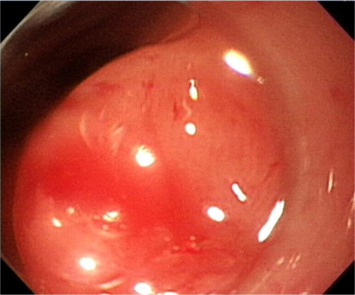

A 41-year-old woman presented to our gastrointestinal outpatient department with a 1-month history of postprandial abdominal fullness and early satiety. No significant abnormality was noted on physical examination and laboratory tests. Esophagogastroduodenoscopy (EGD) showed the presence of two small polypoid lesions (1.2 cm and 0.8 cm in size) with intact mucosa in the gastric antrum (Fig. 1 ). Endoscopic ultrasonography (EUS) indicated two oval, hypoechoic, and homogeneous lesions appearing to involve the muscularis mucosa and submucosa (Fig. 2 ). We suggested a “wait-and-see” strategy because a benign etiology was more favored. However, the patient was worried about the possibility of a malignant potential and decided, after discussion, to receive endoscopic resection. Informed consent was obtained and the patient was sedated with an intravenous administration of midazolam. We then performed cap-assisted EMR at our endoscopy unit.

Esophagogastroduodenoscopy shows two polypoid lesions in the antrum (1.2 cm and ...

Figure 1.

Esophagogastroduodenoscopy shows two polypoid lesions in the antrum (1.2 cm and 0.8 cm; arrows).